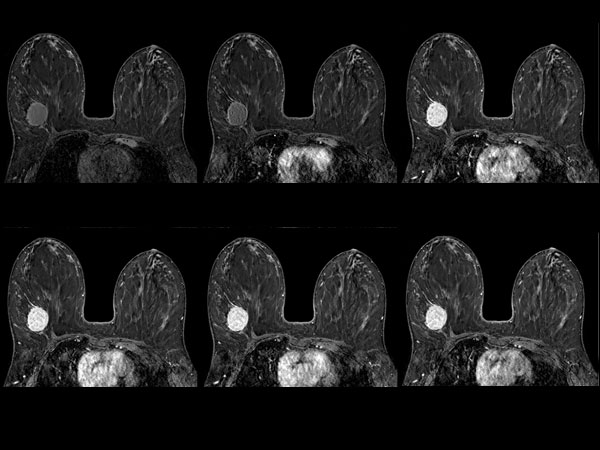

SmartBreast - dS Breast 7ch coil

Utrecht Medical Center, The Netherlands

Used Solution

• System

• Coil